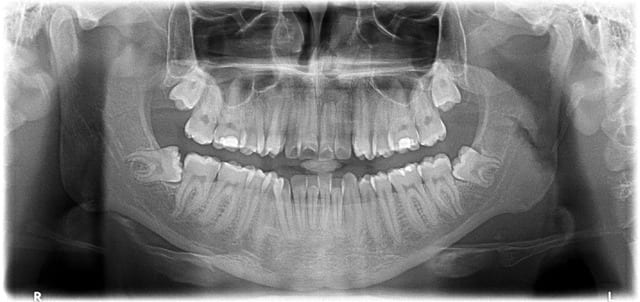

Patient, 20 ans, choc multiples sur les centrales étant gamin. Pano pour les 8.

Lésion sur 21, en bouche, légère dyschromie, test froid négatif, pas de douleur, retro, tu m'étonnes ... ! Les autres répondent correctement.